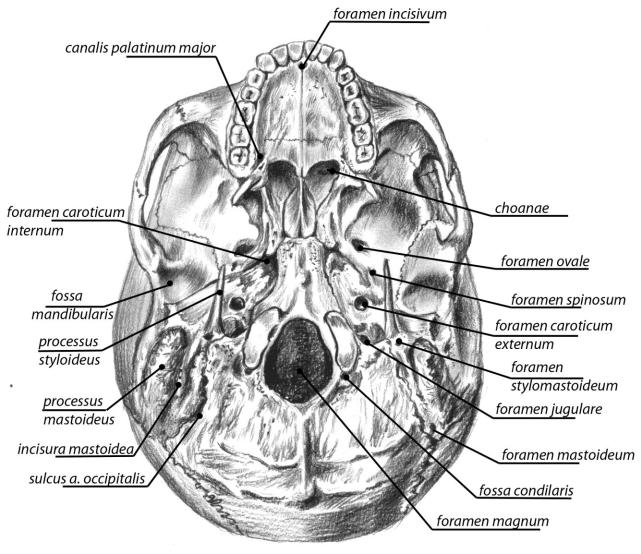

Анатомические детали: Фотографии топографии черепа с нижнего вида

Раздел: Альбом идей